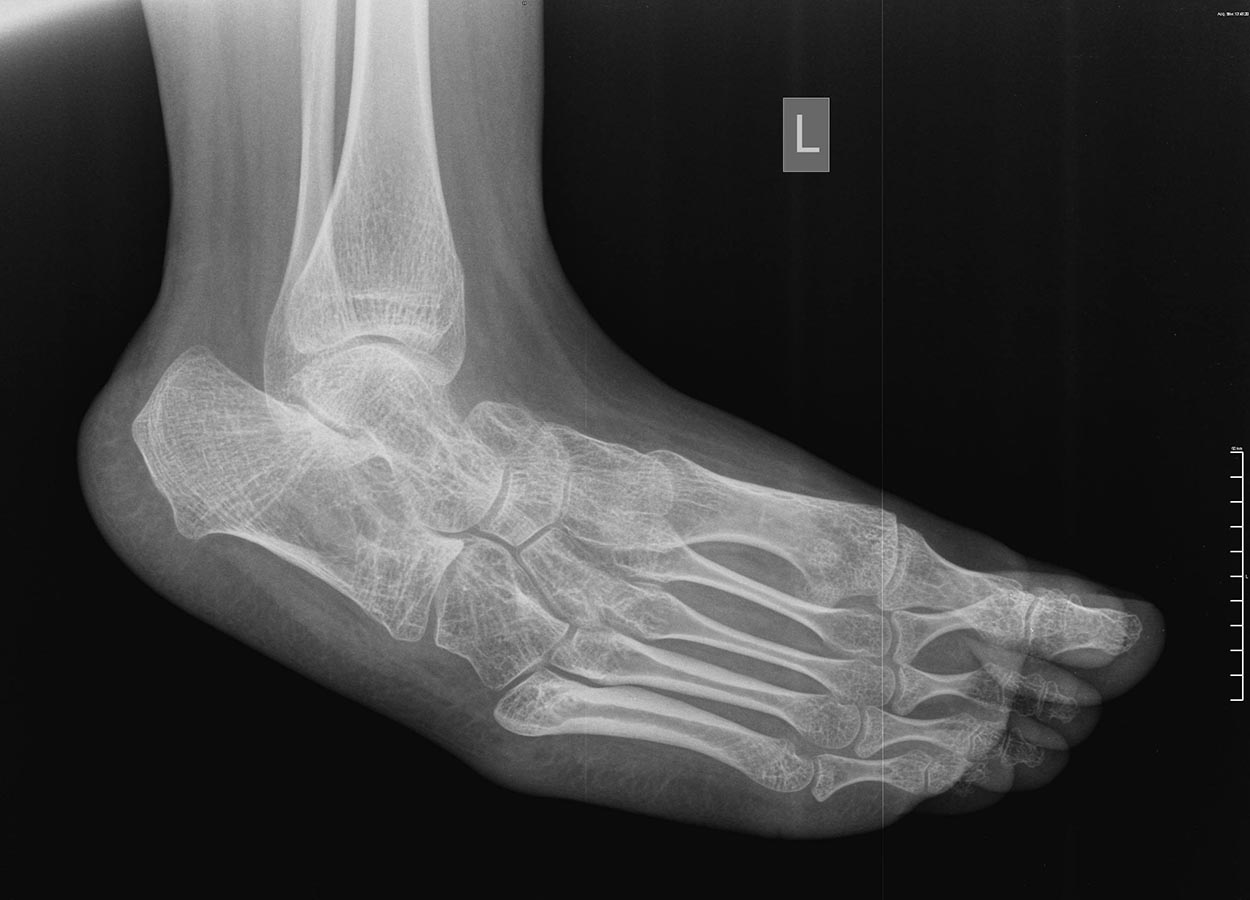

Девочка 15-и лет, страдает ДЦП, квадриплегия, хорошо "разработана", в

8-и летнем возрасте была проведена тенотомия икроножных мышц в

подколенной ямке и приводящих, периодически проходит агрессивную

разработку. До последнего времни могла ходит при помощи палочки, на

ногах AFO. Последний год из-за выраженной эквино-варусной деформации

обеих стоп не может носить ортезы и всвязи с этим ходит при помощи

поддержки матери, стала "колясочной". Учится на отлично! Пассивно стопы

выводятся из эквинуса спокойно, до +5 градусов тыльного

сгибания, в подтаранных суставах пассивные движения отсутствуют,